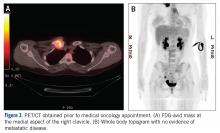

The patient was evaluated by a pediatric hematologist/oncologist 2 weeks later after having obtained the biopsy and a PET/CT scan. At that time, the PET/CT showed an FDG-avid mass at the clavicle without evidence of pulmonary metastatic disease (Figure 3) . She was subsequently evaluated by orthopedic oncology, at which time a discussion was had regarding further treatment. There was essentially no literature to guide the surgical and medical teams, as low-grade clavicular OS is unknown. Based on the evidence of localized, low-grade disease, the determination was made to proceedwith surgical resection. In the event that high-grade disease was identified at the time of final pathological evaluation, the pediatric hematology/oncology team felt that administering all of the patient’s chemotherapy postoperatively would be acceptable and not affect her long-term prognosis. CT and CT angiogram were obtained for further operative planning (Figure 4) .